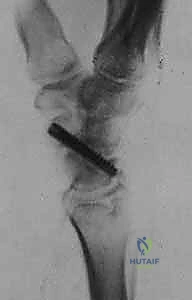

- الاستئصال الدقيق: باستخدام أدوات جراحية ميكروسكوبية دقيقة، يتم استئصال حوالي 3 إلى 4 مليمترات من القطب البعيد للعظم الزورقي. هذه الكمية كافية لمنع الاحتكاك مع عظم الكعبرة، وفي نفس الوقت تحافظ على استقرار الأربطة.

- تقييم المفصل: يتم فحص باقي عظام الرسغ للتأكد من عدم وجود خشونة متقدمة في أماكن أخرى.

- الإغلاق والخياطة: تُغلق كبسولة المفصل والجلد بخيوط تجميلية دقيقة لتقليل الندبات، ثم يُوضع الرسغ في جبيرة داعمة.